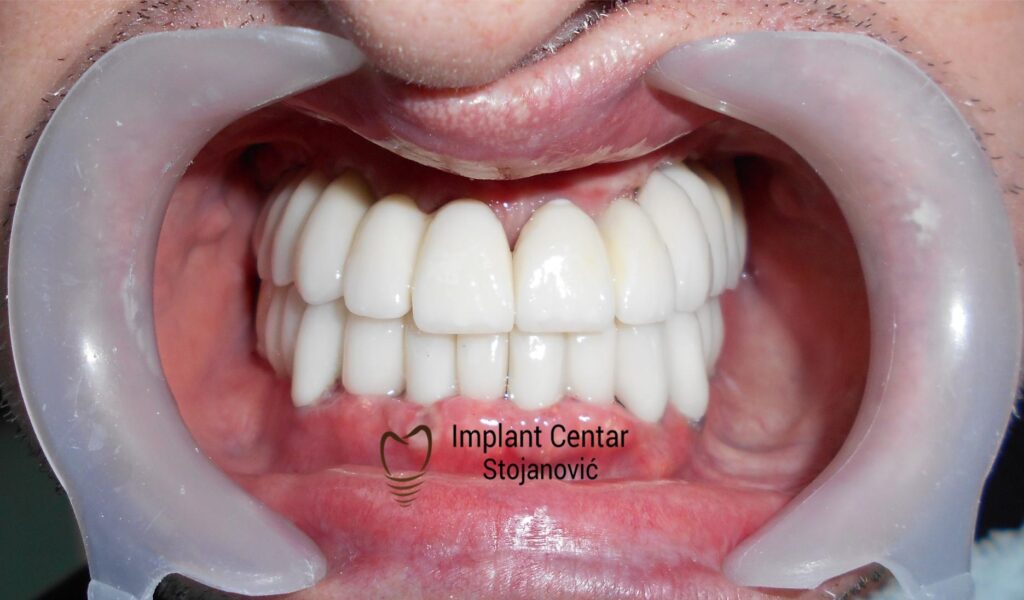

Tokom perioda oseointegracije, pacijent je bio zbrinut fiksnim privremenim krunicama, čime je već pet dana nakon intervencije obezbeđena potpuna funkcionalna i estetska rehabilitacija. Nakon završetka perioda integracije implantata, izrađeni su definitivni cirkonijum-keramički mostovi na implantatima.

Pacijent je izuzetno zadovoljan postignutim rezultatom, navodeći da po prvi put jasno oseća svoje nepce tokom žvakanja, kao i da se smeje sa punim samopouzdanjem.